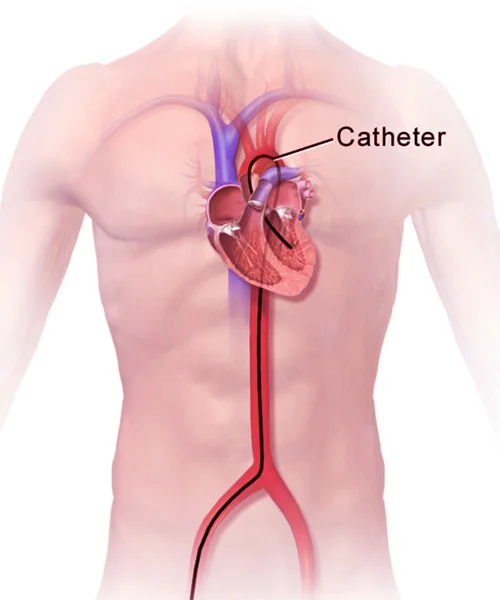

He holds prestigious qualifications including MBBS, MD in General Medicine, and DM in Cardiology, making him a highly skilled expert in interventional cardiology. Dr. Yogesh Nagendra has extensive expertise in procedures such as angiography, angioplasty, pacemaker implantation, Balloon Mitral Valvotomy (BMV), ECHO, and TMT, ensuring accurate diagnosis and effective treatment for every patient.